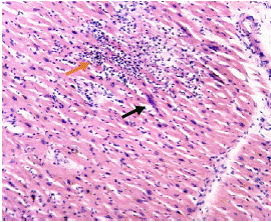

A pesar del tratamiento, la paciente evolucionó rápidamente a una falla orgánica múltiple y falleció a los diez días del ingreso. Se hizo la autopsia y en el estudio histopatológico de tejido miocárdico, cerebral y de músculo esquelético, se encontraron quistes tisulares con formas sugestivas de bradizoítos de Toxoplasma gondii (figura 3 4, 5 6, 7). Estos se sometieron al estudio de inmunohistoquímica utilizando el anticuerpo monoclonal específico para la proteína de membrana P30 de T. gondii (Novocastra™, clon TP3), purificado a partir de líquido ascítico de ratón y diluido en una solución tampón de fosfato salino (PBS), pH 7,6, con albúmina de suero bovino (BSA) al 1 % y 0,09 % de azida de sodio, cuyo resultado confirmó la presencia del parásito en los tejidos evaluados (figuras 8-9-10).

Figura 3 Músculo cardiaco con extenso infiltrado inflamatorio mononuclear (flecha naranja) y un quiste en la fibra muscular con formas sugestivas de bradizoítos (flecha negra). Hematoxilina y eosina, 4X.